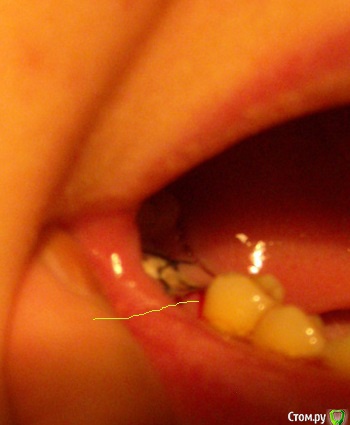

ElviraS Опубликовано 7 ноября, 2015 Поделиться Опубликовано 7 ноября, 2015 (изменено) Здравствуйте. Сегодня третий день после удаления нижней "шестерки" кровит место второго укола (первый зажил нормально, в мышцу). Кололи в "5-ку", под десну - интралигаментарная анестезия. Третий день кровит место укола и боль бьет вниз. Вздутия нет, но покраснение в этом месте есть и вижу сочащуюся кровь. Это нормально что уже третьи сутки болит место от этого укола? Такое чувство что игла вошла не туда куда надо. Раньше никогда не было чтобы так болело место укола и отдавало куда-то.Может ли это нитка тянуть и изза нее кровит? На картинке именно это место кровит и покраснело. Только зуб "5-ка", при удаленной "6-ке". http://www.medenta.ru/medenta/statia/sta3/images/newsta_img_4.jpg Изменено 7 ноября, 2015 пользователем ElviraS Ссылка на комментарий

ElviraS Опубликовано 7 ноября, 2015 Автор Поделиться Опубликовано 7 ноября, 2015 (изменено) обратитесь к вашему лечащему врачувозможно выполоскали кровяной сгусток и/или травмировали область лункиЛунка зашита , и совершенно не беспокоит. А боль именно вплотную к соседнему зубу и кровит из его десны. Сейчас глянула получше - там порезик на десне пятерки, от зуба вниз, миллиметра 3. Темный. Кровь уже запекается но все равно кровит. Видно глубокий, раз не зажил пока. Может ли порезаная десна так долго заживать (третий день боль и кровь (не сильно и иногда нет. но иногда вдруг сочится) и не повредит ли этот порезик моей бедной лунке что он кровит? Я готова потерпеть до четверга (день снятия швов), может он заживет? Изменено 7 ноября, 2015 пользователем ElviraS Ссылка на комментарий

ElviraS Опубликовано 10 ноября, 2015 Автор Поделиться Опубликовано 10 ноября, 2015 (изменено) Как оказалось, шовная нить (в виде крученой проволоки тонкой) порезала десну. такое бывает из-за воспаления в первые дни. У меня на второй день. Сегодня сняли швы - уже немножко но полегчало - чувство натяжения в ране пропало. Так что у кого будет аналогичный порез - дотерпите до снятия швов или сходите к врачу если невмоготу терпеть. Я на ночь пила обезбольки (миг 400) а днем кое как терпела - не хотелось ничего менять - шов на лунке слишком хорошо лежал. Изменено 10 ноября, 2015 пользователем ElviraS Ссылка на комментарий